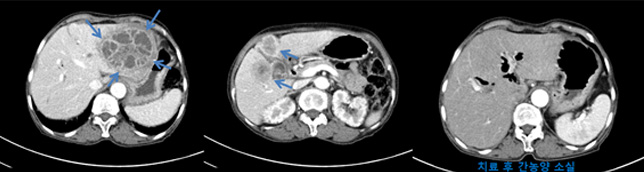

- 세균, 원충, 진균등의 원인균이 간실질내로 침투하여 증식함으로써 간실질내 종괴 양상의 고름을 형성하는 질환입니다.

- 국내에서는 과거 위생상태가 좋지 못했을 때는 아메바성 간농양이 흔했으나, 최근에는 위험요인을 가진 환자에서 화농성 간농양이 증가하고 있습니다.

- 임상양상 ; 증상은 다양합니다. 발열, 복통, 압통등이 있으며, 비특이적 증상으로 오한, 식욕부진, 체중감소, 오심, 구토, 전신쇠약, 무력감이 있습니다.

- 진단 ; 과거에는 불명열의 원인이었으나, 최근에는 영상기술의 발전으로 진단할 수 있습니다. 간초음파, 간복부전산화단층촬영등의 방법으로 진단이 가능합니다.

- 치료 ; 적절한 배농과 항생제로 치료가 가능합니다. 하지만 크기가 크거나 외과적 질환이 동반된 경우 수술을 고려할 수 있습니다.